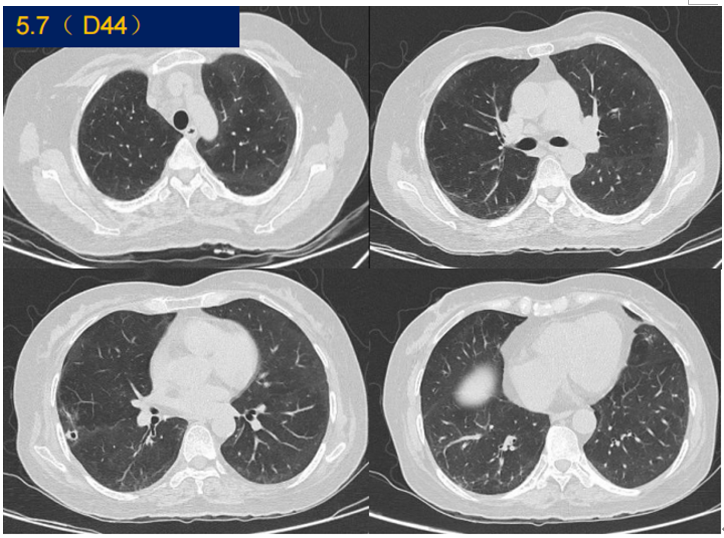

患者,男,56岁;发热5天,加重2小时余,2020年4月26日入我院EICU,4月29日转入RICU。8年前于外院诊断:可疑系统性红斑狼疮,强的松10 mg qd,吗替麦考酚酯片2片bid。检查:Na 124.7 mmol/L,Cr 350 μmol/L,PCT>100 ng/ml,IL-6 3573 pg/ml;氧合指数108 mmHg。胸部CT提示肺部大片实变,脏器功能受损。BALF mNGS(序列数17107)及PCR均提示军团菌,给予莫西沙星抗感染及其他支持治疗(IPPV+CPFA++CPFA),患者最终痊愈出院。

图片

治疗前后胸部CT比较